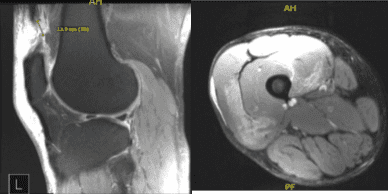

Xray and MRI results were presented and shown and no significant degenerative changes in the Xray. Meanwhile, MRI showed significant result of full-thickness rupture of the distal quadriceps tendon occurring 1.8 cm proximal to the patellar insertion site and resulting in a tear gap measuring up to 1.5 cm. There is accompanying patella Baja and soft tissue edema tracking into the vastus musculature and small to moderate-sized joint effusion.

Right Knee X-ray AP Lateral and Oblique 3 views

MRI-3T Right Knee Non-contrast